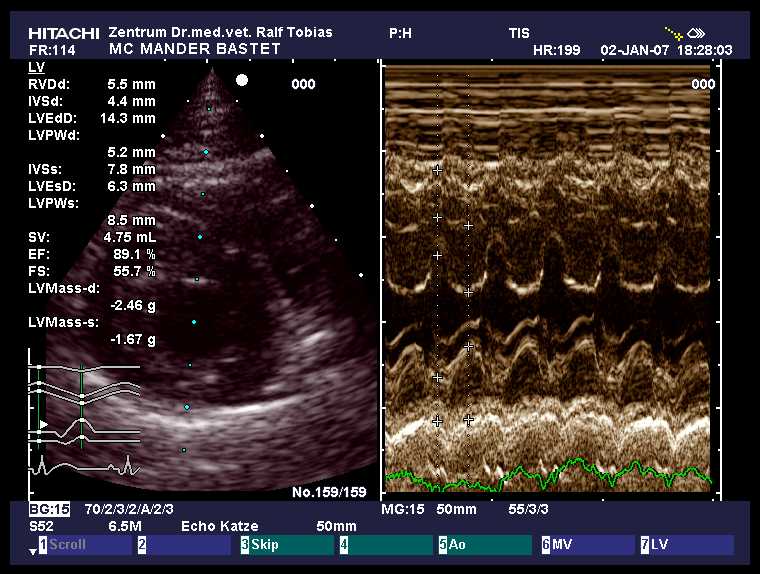

HCM-Schall Januar 2007

|

normal

age: 3y 0m

weight: 4.5 kg

IVSd: 4.7 mm

LVFWd: 4.8 mm

SAM: no

papillary muscles: normal

Dr.Tobias, Hannover